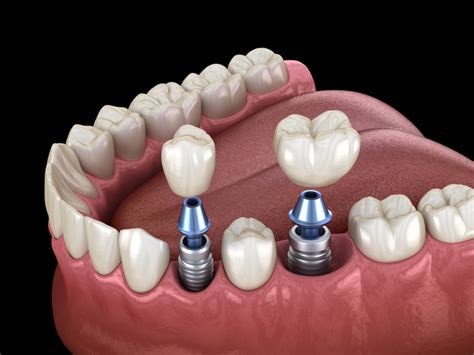

Los implantes dentales se han convertido en una solución popular para reemplazar dientes perdidos. Por lo general, los implantes dentales se integran correctamente en el hueso maxilar y funcionan sin problemas durante muchos años, actuando igual que los dientes naturales. Sin embargo, como cualquier procedimiento quirúrgico, no está exento de complicaciones.

En algunos casos, puede ocurrir un rechazo del implante, lo que puede ser motivo de preocupación para los pacientes. Es fundamental entender que el rechazo de implantes dentales no es lo mismo que las complicaciones postoperatorias. Las complicaciones pueden ser tratadas y, en muchos casos, no afectan la viabilidad del implante a largo plazo.

Planificación inicial incorrecta o problemas durante la cirugía de colocación del implante: la falta de experiencia por parte del implantólogo o el uso de materiales defectuosos o de baja calidad pueden derivar en el fallo del implante. Para evitar este tipo de complicaciones es recomendable ponerse en manos de implantólogos bien formados, experimentados y que trabajan con marcas de calidad contrastada.